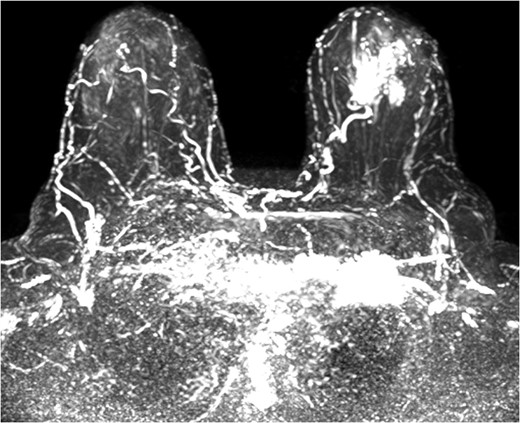

The patient was then sent for MRI of the breast to detail the extent of the remaining mass. This revealed an ill-defined mixed linear and fine nodular enhancing tumor 6.5 × 4.6 × 4.8 cm in size with BI-RADS 5 (Figs 4–7).

The role of MRI in identifying the extent of breast carcinoma is widely reviewed. EPC has been noted to have multifocal hyperintensities at T1 weighted imaging. Contrast MRI will reveal enhancement of the cystic wall, septa and mural nodules [4].